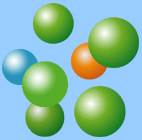

Fig. 2: Map of the z-disc region in the myocardial cell with proteins involved in sarcomeric contraction |